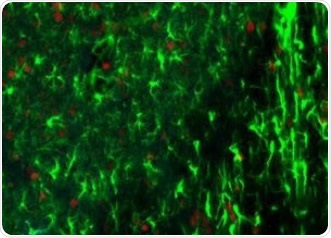

3-D micrometer scale tomography has been enabled by the use of optical sections and can be used to create high-resolution maps of small, stained rodent brains, including the depiction of associated neurons and corresponding processes. Clear images with improved optical resolution (especially in the depth direction), can also be produced using confocal fluorescence techniques where out-of-focus light from the sample that is outside the focal plane is eliminated via a pinhole.

Figure 1. Rodent brain (top) depicting simultaneous acquisition of fluorophores Cy2, Cy3 and Cy5; Brain image (bottom) magnified to 0.5 μm. Image credit: Huron Digital Pathology.

- A greater penetration depth and optical sections enables significant savings on preparation time and improved spatial registration accuracy and precision alignment. When combined with clearing methods such as Scale, it is possible to image thick tissue sections of up to 500μm without reducing the intensity of fluorescent proteins. This is especially useful for observing neural networks of the hippocampus, cerebral cortex and white matter.

- This is the only confocal fluorescence digital slide scanner that enables the simultaneous acquisition of up to three fluorophores spanning the whole visible spectrum, from 400nm-850nm. This provides considerable time-savings and less photo bleaching due to the unique flying-spot laser platform.